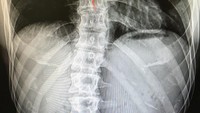

"Aku sudah punya tulang belakang seperti ini sejak SMA. Orang-orang selalu bertanya kepadaku bagaimana aku olahraga dengan tulang belakang ini. Aku hanya mengatakan pada mereka bahwa aku harus membuat sesuatu untuk mendukung tulang belakangku yang melengkung," tulisnya. (Foto: Instagram/kjk76)

#Nevercomplained pecundang selalu mencari alasan untuk tidak percaya. Mereka tidak mau percaya. Ayo lah, lakukan apa yang ingin kamu lakukan. Segalanya jadi mungkin kalau kamu mencoba yang terbaik, tidak peduli kelemahan yang kamu miliki. #Motivation #BPositive #ImpossibleIsNothing," tambahnya. (Foto: Instagram/kjk76)

Aku sudah punya tulang belakang seperti ini sejak SMA. Orang-orang selalu bertanya kepadaku bagaimana aku olahraga dengan tulang belakang ini. Aku hanya mengatakan pada mereka bahwa aku harus membuat sesuatu untuk mendukung tulang belakangku yang melengkung, tulisnya. (Foto: Instagram/kjk76)

#Nevercomplained pecundang selalu mencari alasan untuk tidak percaya. Mereka tidak mau percaya. Ayo lah, lakukan apa yang ingin kamu lakukan. Segalanya jadi mungkin kalau kamu mencoba yang terbaik, tidak peduli kelemahan yang kamu miliki. #Motivation #BPositive #ImpossibleIsNothing, tambahnya. (Foto: Instagram/kjk76)